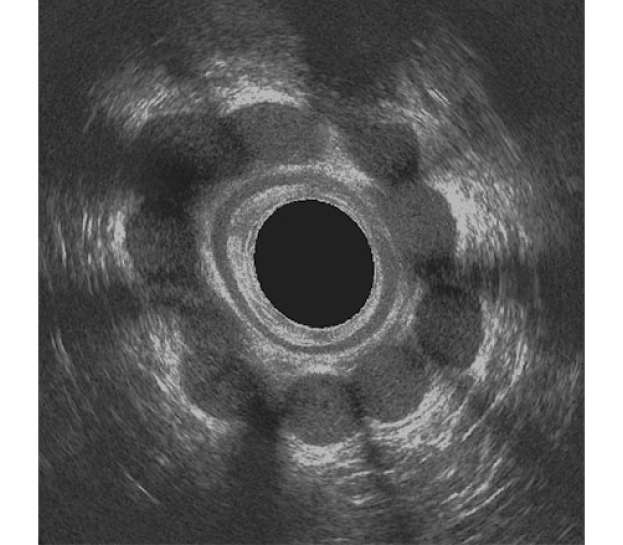

Sphinkeeper Anal İnkontinans İmplantı